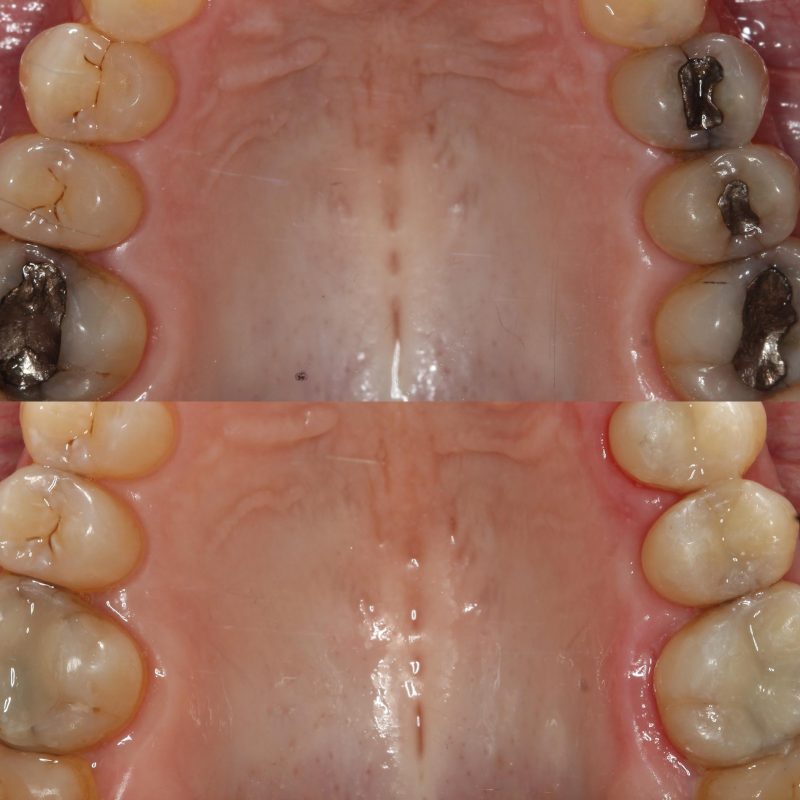

Cuándo cambiar una amalgama dental: señales de que conviene revisarla

Muchas personas llevan empastes de amalgama desde hace años y nunca se han preguntado si siguen en buen estado. Otras sí se lo plantean, pero no saben si deben cambiarlos solo por ser antiguos o únicamente cuando dan problemas. La respuesta corta es esta: no toda amalgama hay que retirarla por sistema, pero sí conviene […]